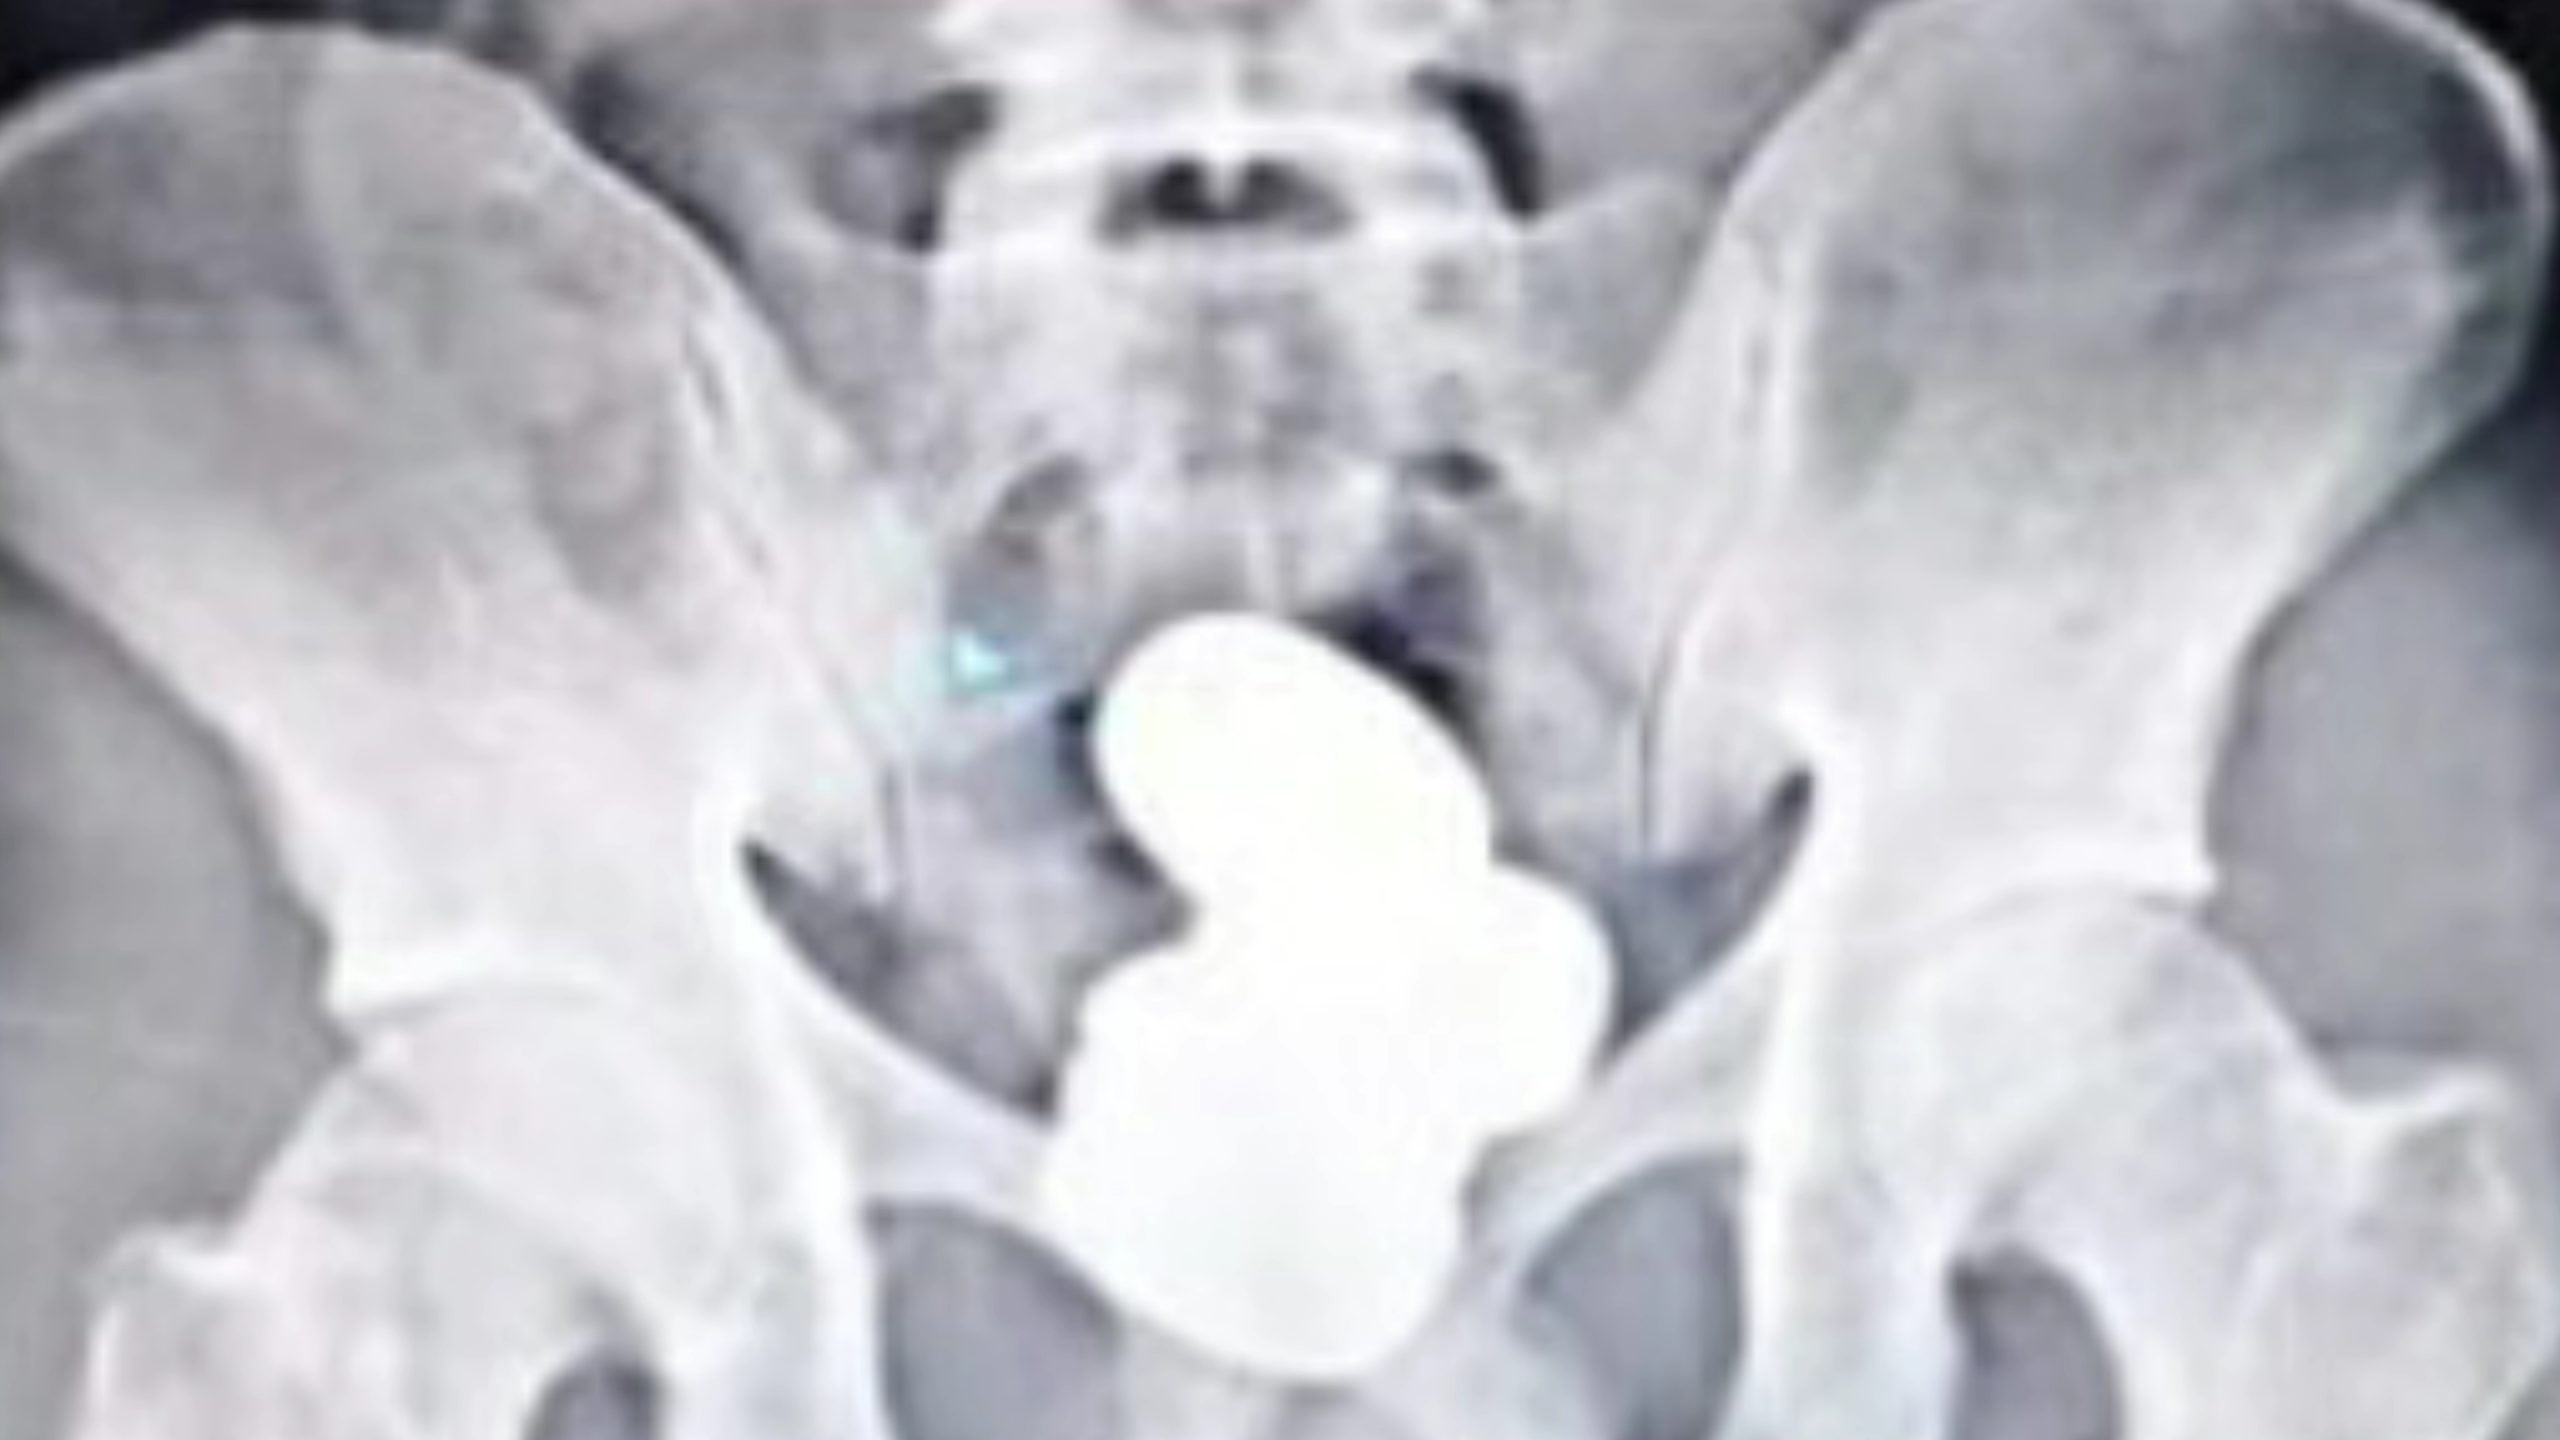

ইয়াৰ পিছতে লোকজনৰ এক্স-ৰে’ কৰাত লোকজনৰ মলদ্বাৰত সোণ থকা ধৰা পৰে। লোকজনৰ পৰা ৪ টা সোণৰ পেকেট জব্দ কৰা হয়। জব্দকৃত ৯০৯.৬৮ গ্ৰাম ওজনৰ সোণখিনিৰ বজাৰ মূল্য প্ৰায় ৪২ লাখ টকা বুলি জানিব পৰা গৈছে।